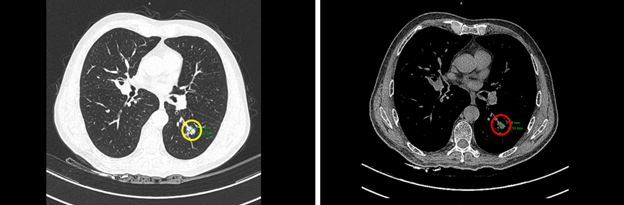

Hình 1: Hình ảnh nốt đặc thùy dưới phổi trái kích thước 10x14mm trên của sổ nhu mô (vòng tròn màu vàng) và cửa sổ trung thất (vòng tròn màu đỏ)